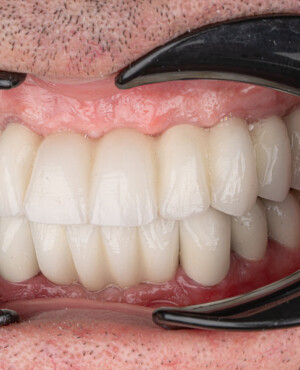

Prin realizarea coronițelor în conformitate cu parametrii exacți ai dinților protezați, această tehnologie asigură atât estetica, cât și funcționalitatea necesare, conferind un aspect natural întregii dentații.

- Aspect estetic natural și calitativ, care permite refacerea armonioasă a zâmbetului;

- Funcționalitate completă, asigurând procesul normal de masticație;

- Rezistență și durabilitate, cu o durată medie de viață de aproximativ 8 ani;